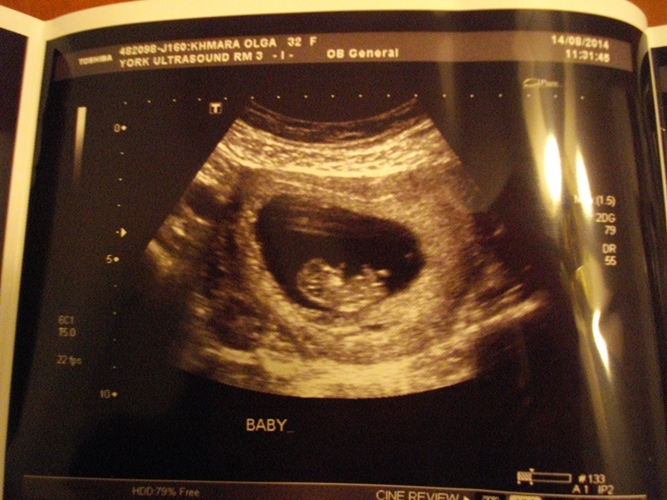

Привет, девочки мои золотые!))) Ну что, сегодня были на первом УЗИ))) Все хорошо у нас, слава Богу. По месячным срок ставят 9 недель и 4 дня, а по УЗИ - 10 недель и 2 дня. Почему - не знаю ни фига, да и все равно мне. Передвинули ПДР с 15 марта на 10-е))) С Наташей у меня ПДР был 5 марта тоже))) Клево)))

Видели нашего головастика, такой классный!!!! Пока папы не было в кабинете, спал и дал себя всего померить))) А как папу запустили в кабинет, с Наташей, сразу ручками замахал, ножками зашевелил - такой лааааапка! Послушали сердечко))) Наташа под впечатлением! Следующее УЗИ, сказали в 12-13 недель вроде. А вот и мы)))![]()